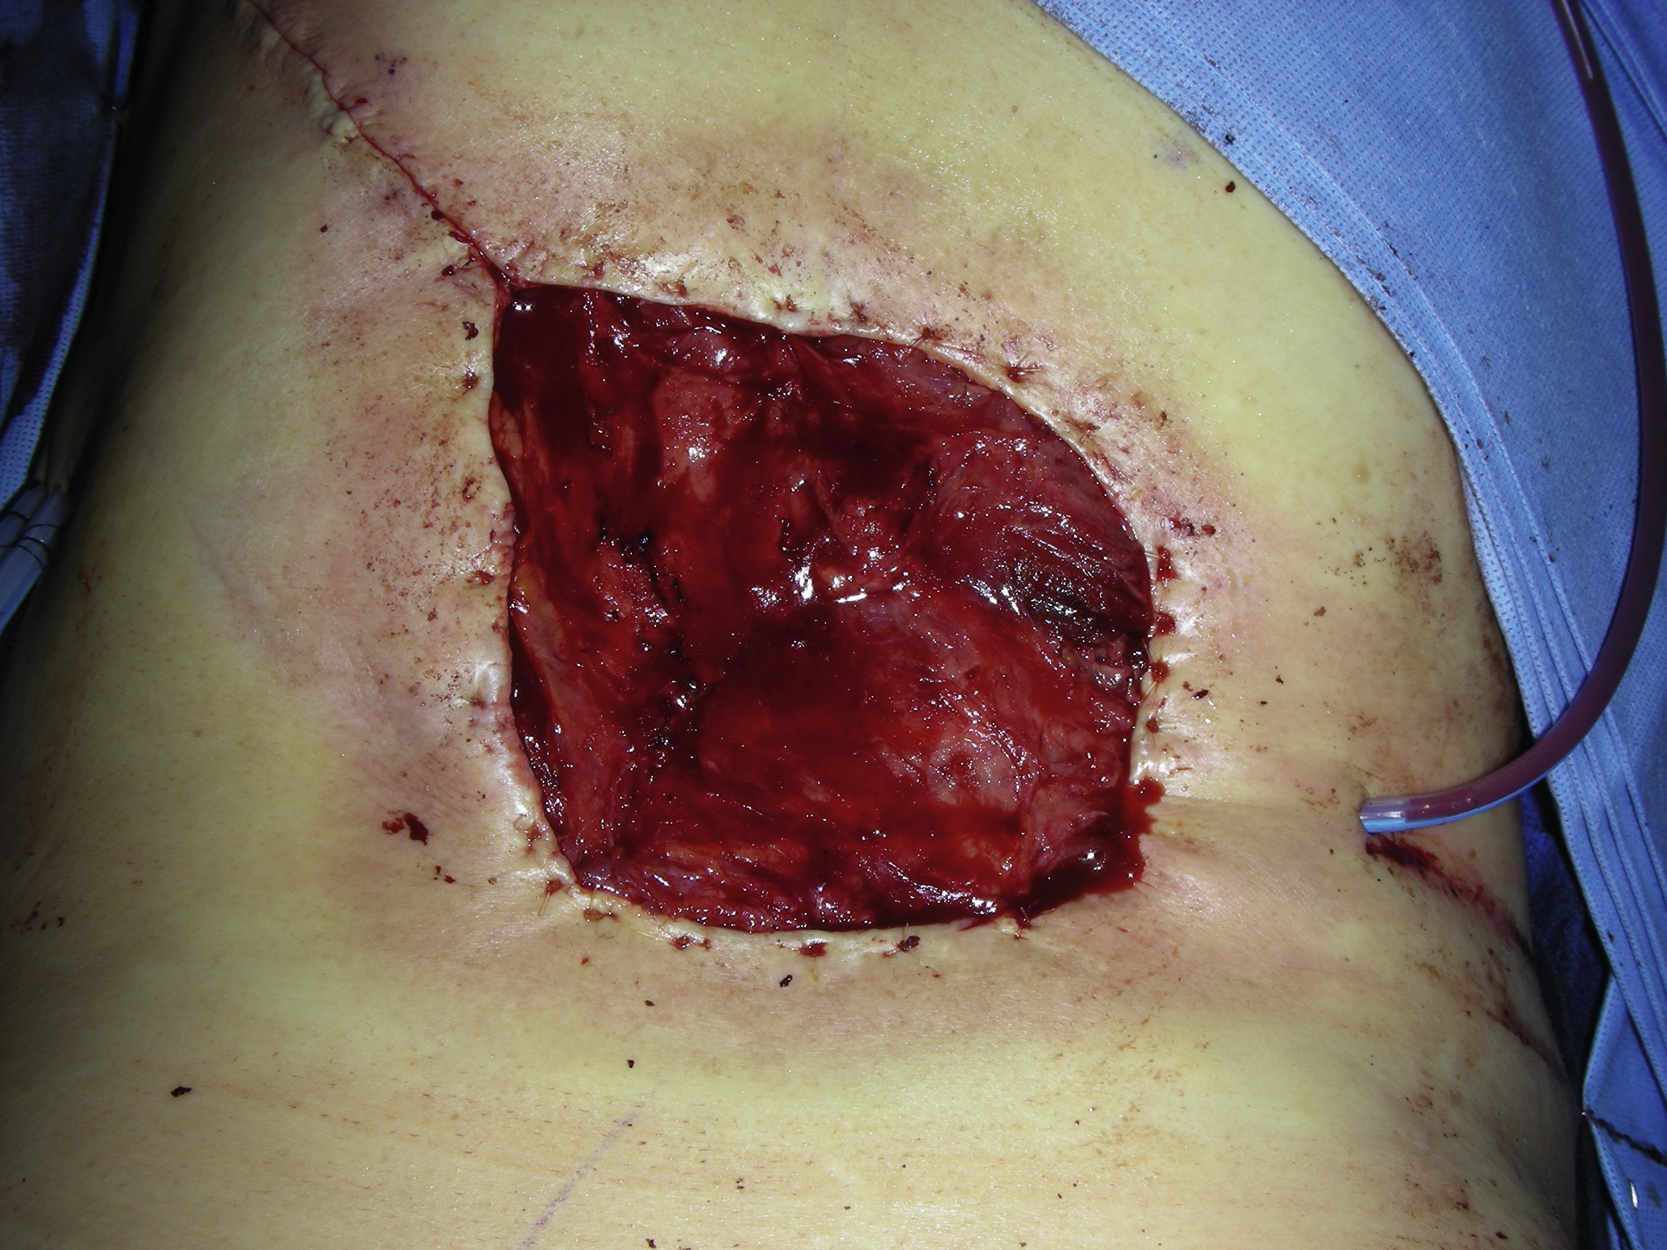

Under general anesthesia with the patient in a prone position, the wound was debrided by the neurosurgery service. The wound was located from T12 to L4 and measured 10 × 9 cm ( Fig. 29.2 ). There were necrotic tissues on the surface with fibrotic tissues along all the edges of the wound. The wound was sharply debrided and all the visible necrotic or colonized tissues were removed. The wound was then irrigated thoroughly with Pulsavac.

Several major perforators for each side of the latissimus muscle flap were identified by a duplex scan. This flap could be based on the 3–5 major perforators along the same side of the thoracic spine. Two larger perforators were identified on the left side and the left latissimus muscle was selected for the flap reconstruction ( Fig. 29.3 ). An oblique incision was made to explore the pedicle vessels of the left latissimus muscle. The skin flap was raised on either side of the latissimus muscle. Once the medial and the lateral border of the latissimus muscle had been identified, the dissection was performed toward the left axilla. The thoracodorsal vessels were identified and divided with hemoclips. The muscle was divided from its proximal insertion and elevated along with the submuscular tissue plane. By further dissection around those perforators, the latissimus dorsi muscle flap was turned over to cover the wound without too much tension ( Fig. 29.4 ).